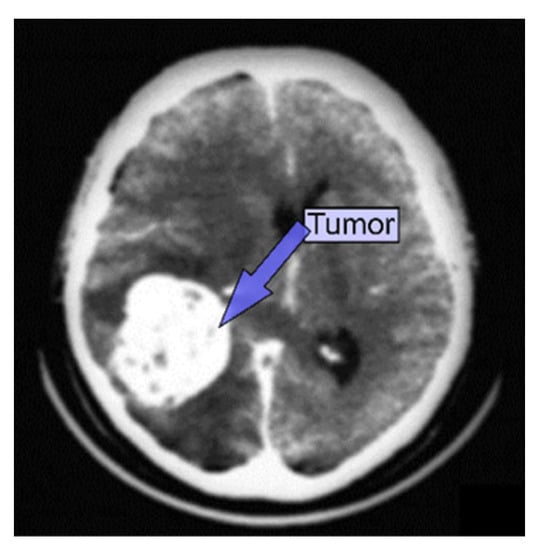

3.2. CT

5.3.5. Various Segmentation and Classification Methods Employing CT Images